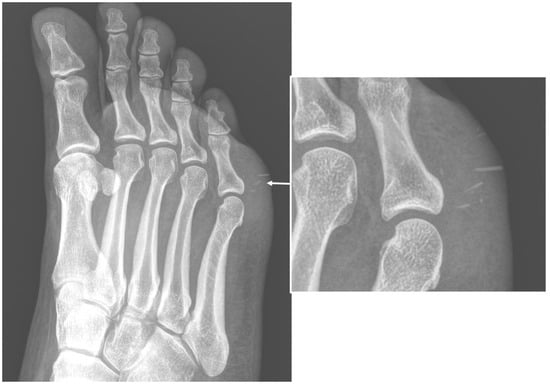

2.3. Soft-Tissue Foreign Body